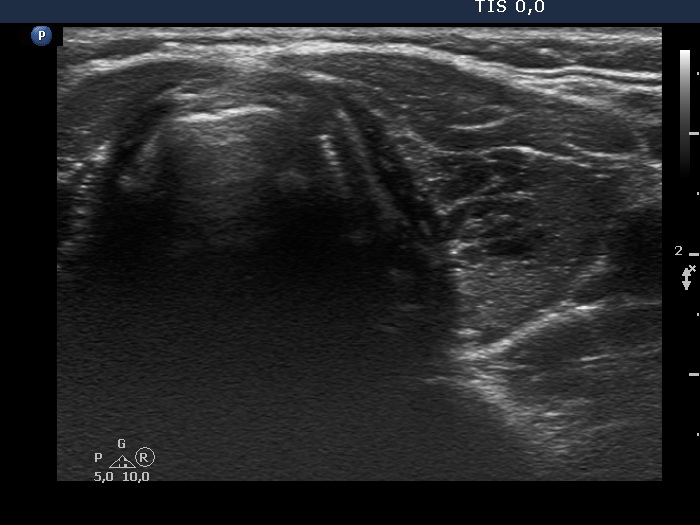

Ultrasonography. The thyroid was minimally hypoechogenic and had several discrete more hypoechogenic areas, including a cluster composed of multiple discrete lesions in the dorsal part of the left lobe. These lesions had irregular, partly lobulated, partly spiculated margins. However, the entire pattern corresponded to Hashimoto's thyroiditis.

Regarding the nodule borders the lesions presented partly lobulated, partly spiculated margins. However, these should not be held as pathological nodules, the discrete lesions are presentations of more active foci of Hashimoto's thyroiditis, which is an infiltrative process and therefore frequently has infiltrative, irregular margins.